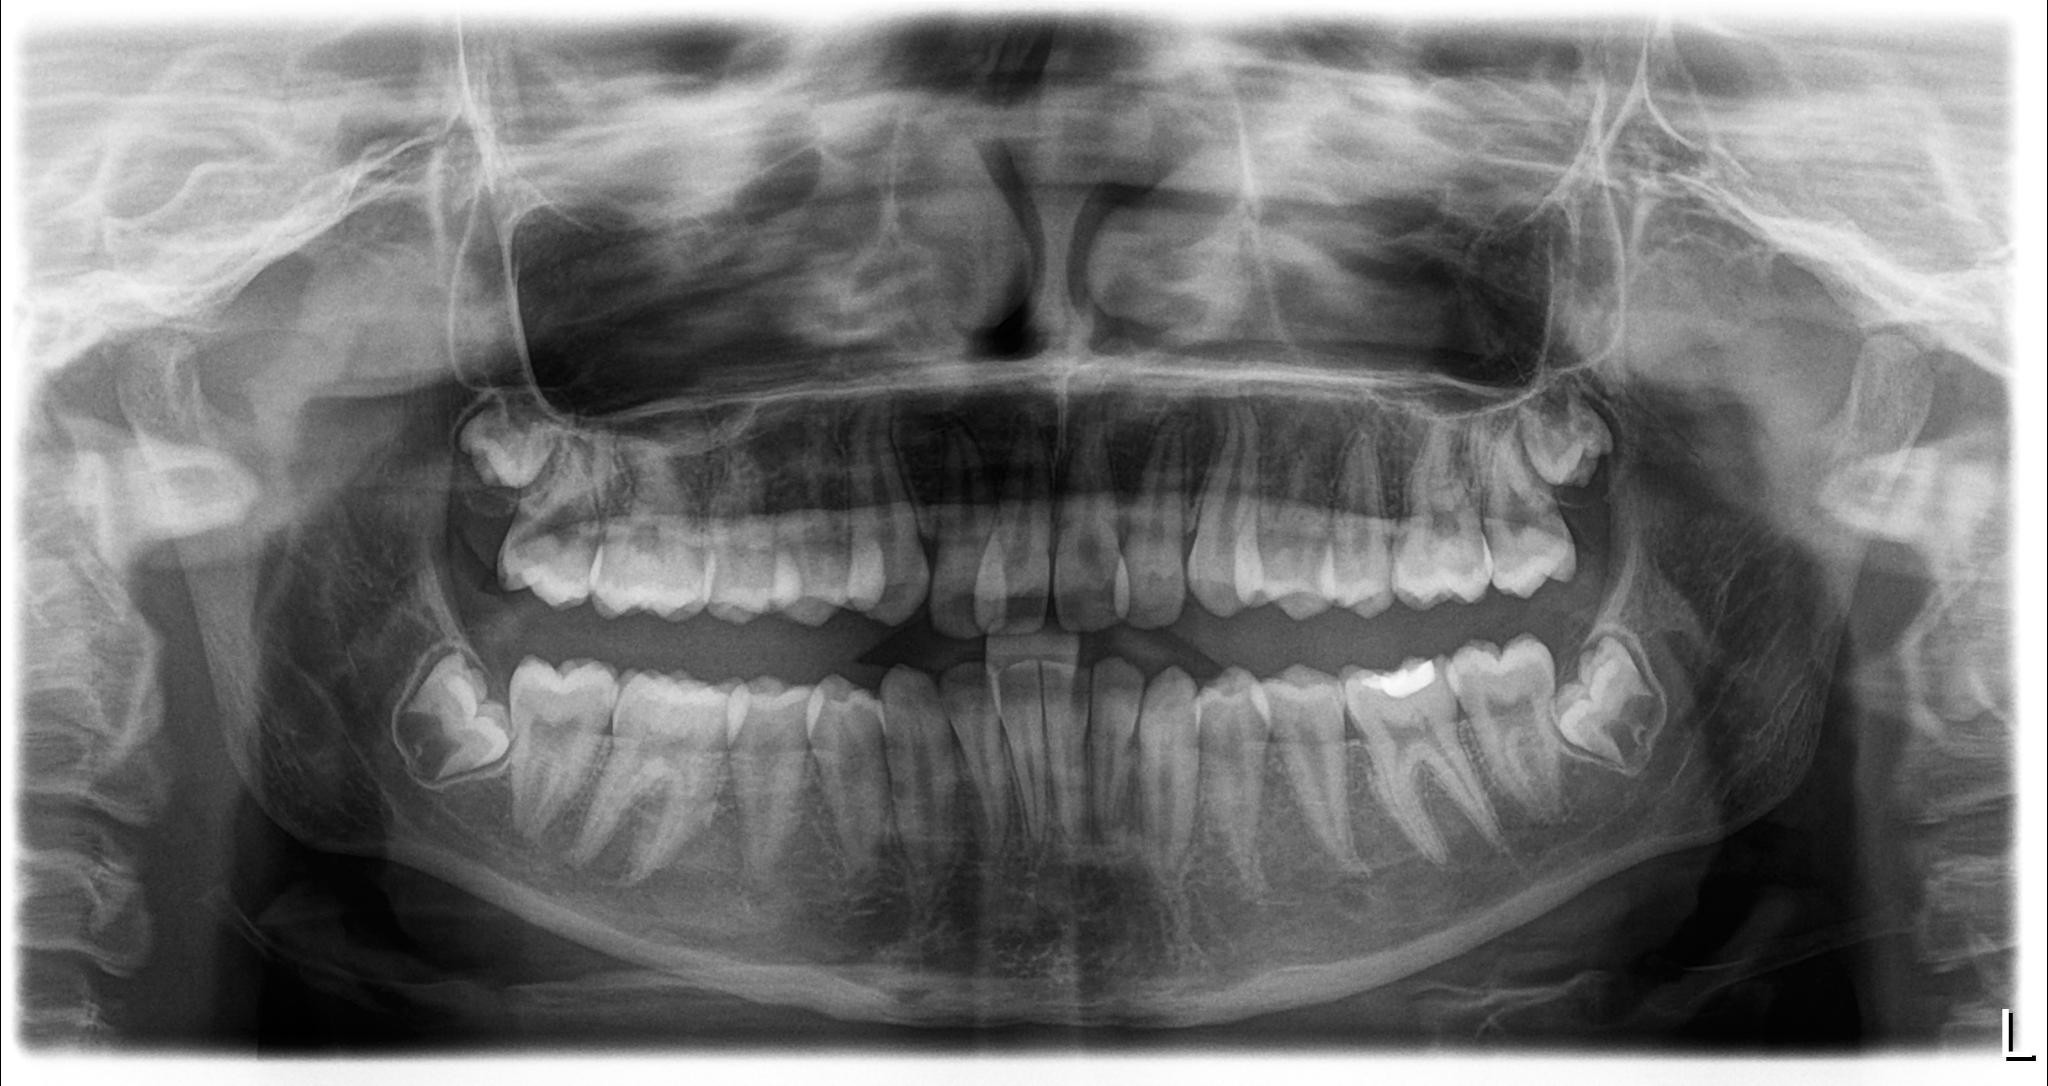

- Restricted tongue mobility (ankyloglossia)

- Open bite and anterior dental crowding

- Orthodontic correction for open bite and crowding